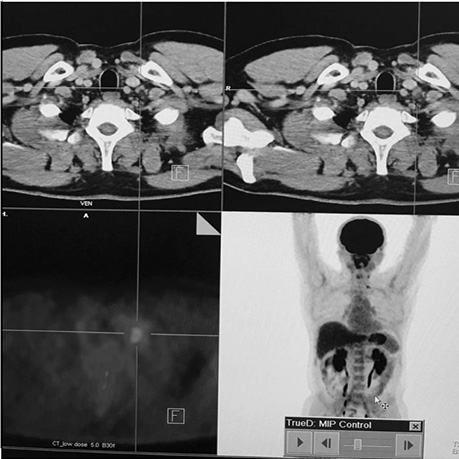

Хворий А., папілярний рак щитоподібної залози, 4 курси РЙТ, відсутність накопичення 131I-NaI на постлікувальному скані після 3-го курсу. За даними УЗД та КТ обстеження — підозра на можливі вогнища в зоні шиї та легень. Хворому назначено ПЕТ / КТ з 18F-ФДГ (рис. 4, 5).

Рис. 4. ПЕТ / КТ з 18F-ФДГ. Візуалізується вогнище гіперфіксації 18F-ФДГ в надключичній зоні справа

Рис. 5. ПЕТ / КТ з 18F-ФДГ. Візуалізується вогнище в зоні шиї

За даними ПЕТ / КТ з 18F-ФДГ у цього пацієнта підтверджено наявність вогнища гіперфіксації РФП в зоні шиї, водночас не виявлено ознак пролонгації процесу в легенях. Вірогідно, ідентифіковані вогнища за даними КТ відповідають фіброзним змінам після перенесених запальних процесів.

Після проведення діагностичного обстеження хворому призначено таргетну терапію препаратом Нексавар® згідно з протоколом лікування.

Діагностичне сканування з 18F-ФДГ допомогло виявити зниження функціональної активності вогнища в зоні шиї (SUV — 6,9–4,2). Зменшення розміру вогнища не відмічалося (рис. 6).

Рис. 6. ПЕТ / КТ з 18F-ФДГ. Вогнище гіперфіксації 18F-ФДГ у надключичній зоні справа, метаболічне зображення після проведення таргетної терапії